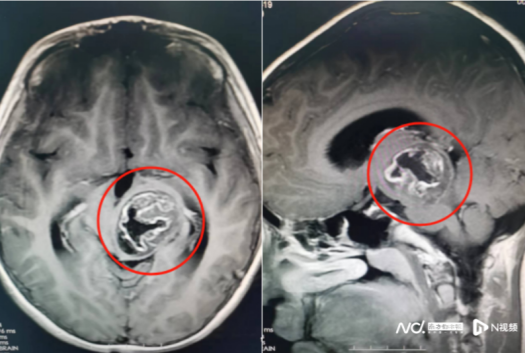

脑部检查结果提示,轩仔的左侧丘脑、中脑存在占位性病变,大小约为39mm×30mm×35mm。该院副院长鲁明在接诊时,发现患儿左眼斜视明显、右上肢肌力下降,推断是脑肿瘤引起的症状。

术前影像资料。